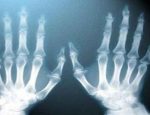

الأخيرة صور الأشعة أصبحت ملونة أجرى علماء في نيوزيلندا أول صورة ملونة بالأشعة السينية بالأبعاد الثلاثية على إنسان، مستعينين بتقنية من شأنها أن تحسن التشخيص الطبي، بحسب ما قالت منظمة… access_timeمنذ 8 سنواتfolder_openالأشعة